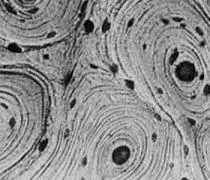

El tejido óseo comparte la naturaleza básica del tejido conjuntivo, ya que está compuesto por células y una matriz extracelular. Sin embargo, a diferencia de otros tejidos conjuntivos, el tejido óseo se distingue por la mineralización de su matriz extracelular.

La característica clave que distingue al tejido óseo es la presencia de una matriz extracelular mineralizada. Esta mineralización se logra mediante la deposición de cristales de hidroxiapatita, que es un fosfato de calcio [Ca10(PO4)6(OH)2]. Esta mineralización confiere al tejido óseo una dureza excepcional, proporcionando el soporte estructural necesario para el cuerpo.